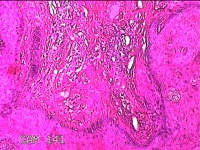

右侧头皮息肉

性别

男

年龄

46岁

临床诊断

一般病史

发现右侧头皮息肉2年余。

标本名称

大体所见

带皮肤组织2x1.2x0.8cm一块,表面光滑,切面灰白粉红色,质中。